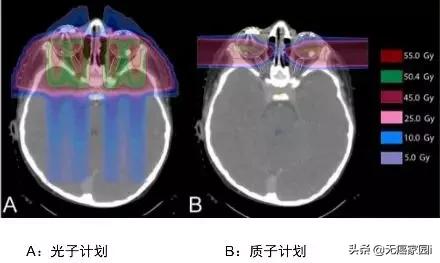

这个是儿童颅咽管癌的IMRT(上图:调强放疗,一种传统放疗的高端模式)与质子治疗(下图:Proton Therapy)的照射剂量分布比较,我们看箭头的指示,传统放疗照射剂量波及的范围很大,虽然颜色很淡(蓝色表示剂量低,黄色表示剂量高),但是需要多个方向同时照射才能达到肿瘤部位的致死剂量,对病灶周边正常组织的危害很大,容易引起严重的副作用,而质子治疗对健康组织的影响会小很多。